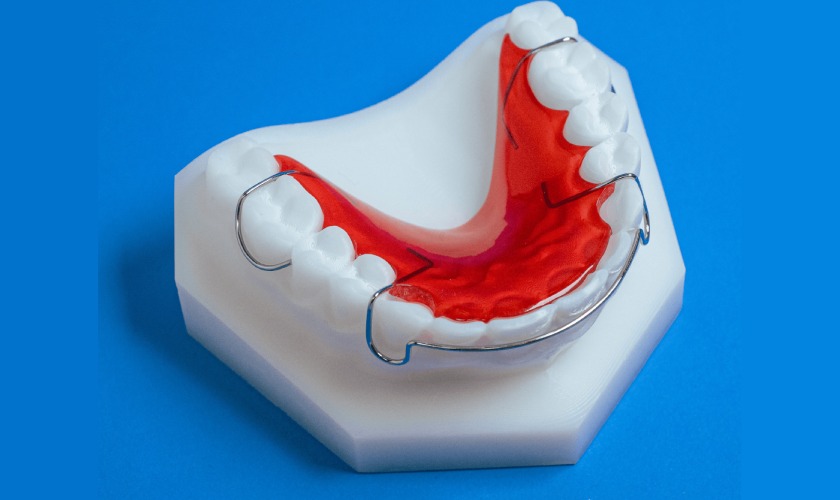

Máng nắn chỉnh răng

Máng nắn chỉnh răng là gì? Có hiệu quả không và chi phí mới nhất 2026